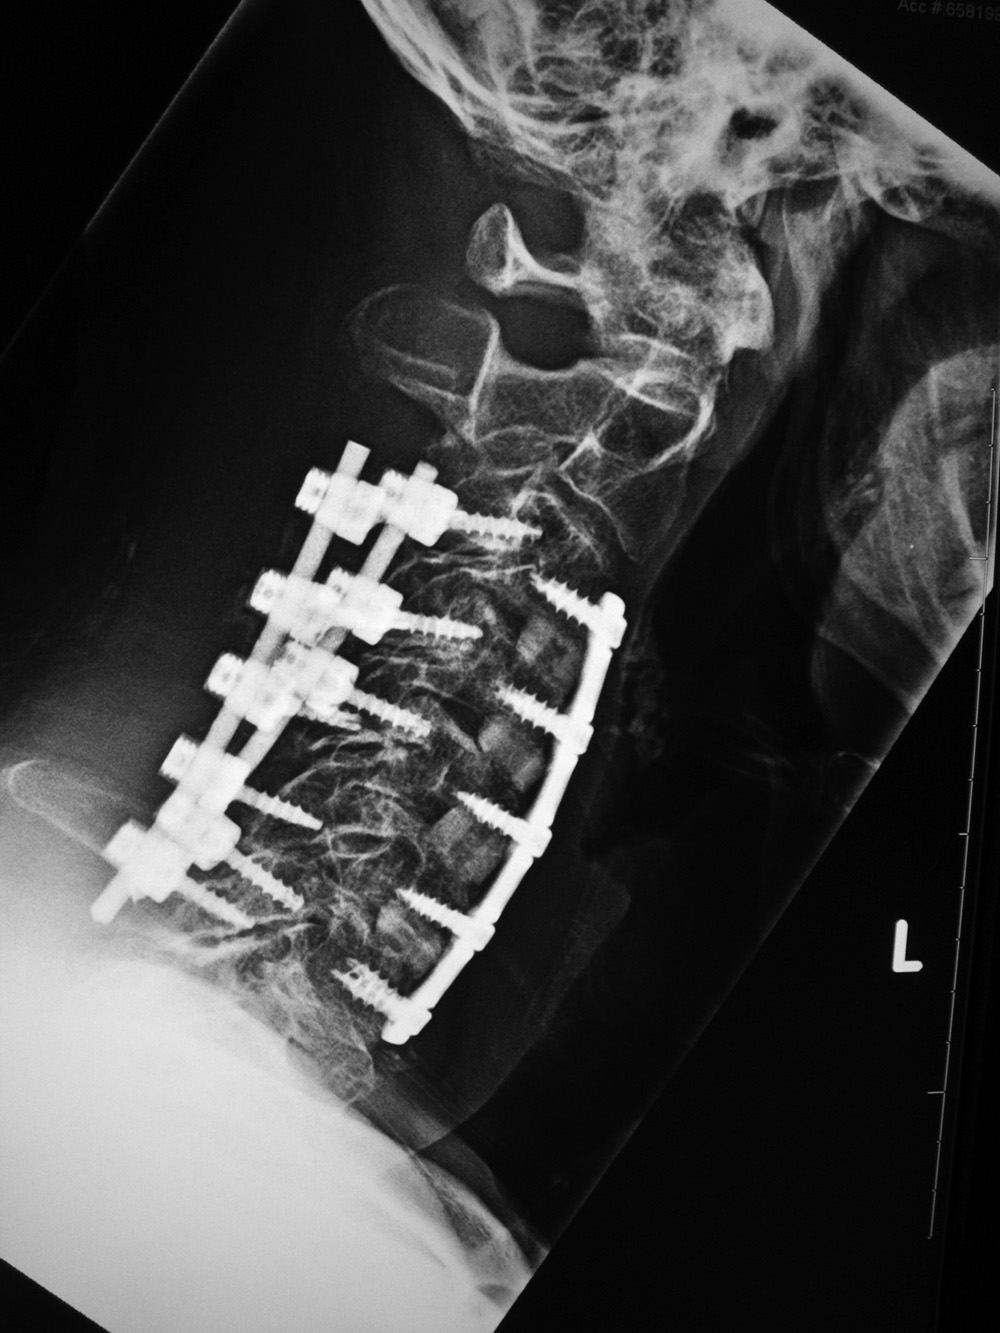

| 53 year-old man with congenital cervical spine fusion and traumatic fracture through fusion mass at C3-7. The spine is stabilized by surgical fusion hardware from the occiput to T2 plus a halo brace. |